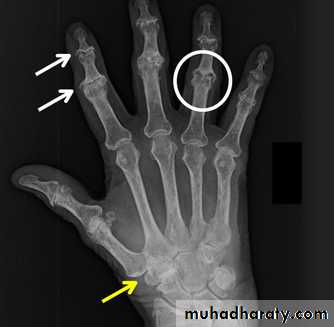

Rheumatoid arthritis.

(A) The initial radiograph shows a hint of early trabecular loss around the proximal interphalangeal joint of a finger with preservation of the joint space and early marginal cortical loss at thebase of the middle phalanx.

(B) The subsequent radiograph shows established erosive change in the area of ill-defined demineralisation in association with joint space narrowing .

Gross rheumatoid arthritis at the carpus with ulnar deviation,

subluxation and joint narrowing at the metacarpophalangeal joints.Boutonniere deformities are present at the index and little fingers.

• Rheumatoid arthritis. Bilateral changes are fairly symmetrical. Soft-tissue swelling is demonstrated, especially over the ulnar styloids. Erosions are demonstrated at the carpus, distal radius and ulna, with joint space narrowing and collapse of bone. Metacarpophalangeal erosions are also seen associated with joint space narrowing. There is a swan-neck deformity of the right fifth distal interphalangeal joint